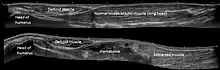

Chef long du muscle biceps brachial

Le chef long voit son tendon perforer la capsule de l'articulation gléno-humérale, passer à l'intérieur de cette capsule, puis poursuivre dans une gaine synoviale dans le sillon intertuberculaire de l'humérus entre le grand et le petit tubercule de l'humérus. Il est retenu dans cette coulisse par le ligament transverse huméral.

Les deux chefs se rejoignent approximativement à mi-bras.